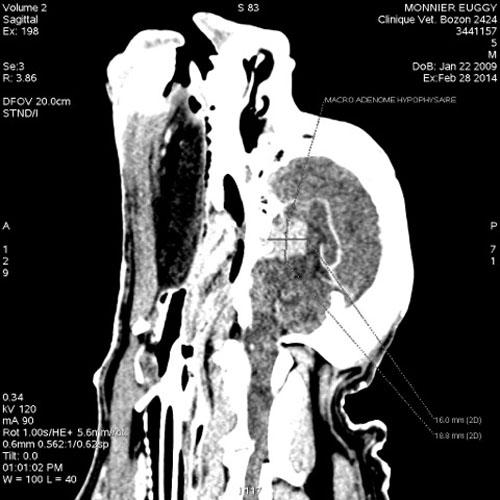

• Scanner (réalisé par la Clinique Vétérinaire Bozon à Versailles) : (photos)

• Mise en évidence d’un volumineux macroadénome hypophysaire de 19,2 x 15,3 x 13,3 mm